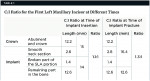

An unfavorable crown-to-implant ratio (C:I) is considered to be a compromising biomechanical factor pertaining to prosthesis design in implant-supported restorations.8 When determining long-term prognosis, the literature is scarce on the validity of the C:I ratio as well as crown-to-root ratio.9 Another potentially significant biomechanical factor to consider is crown height space (CHS), which is determined by measuring from the crest of the alveolar bone to the occlusal surface or incisal edge of the crown.10,11 The clinical C:I ratio is calculated from the segment outside the alveolar bone (because the fulcrum is located at the bone crest) to the implant length residing in the bone.12 A ratio of greater than 1:1 is the minimum acceptable ratio for a prospective abutment, but these guidelines are empirical and lack scientific validation.9,13

At the time of the first definitive restoration placement, the C:I ratio was 1.1:1. This progressed to a ratio of 1.3:1 (Table 1). The average C:I ratio of a single-tooth implant-supported restoration exceeds that which is considered favorable for a natural tooth.9 In the patient presented, this is an average ratio, which results from the use of a long implant (14 mm SLA surface). The use of a shorter implant would have worsened the C:I ratio. Occlusal overload is another factor to consider. Biomechanical stress distribution in supporting bone around an implant is minimized by reducing nonaxial loading of dental implants.14 After placing implant-supported restorations, it is advisable to provide patients with custom acrylic resin occlusal devices to protect the definitive restorations from occlusal overload. Non-compliance with the device must be discussed with patients as a contributing factor to future complications.